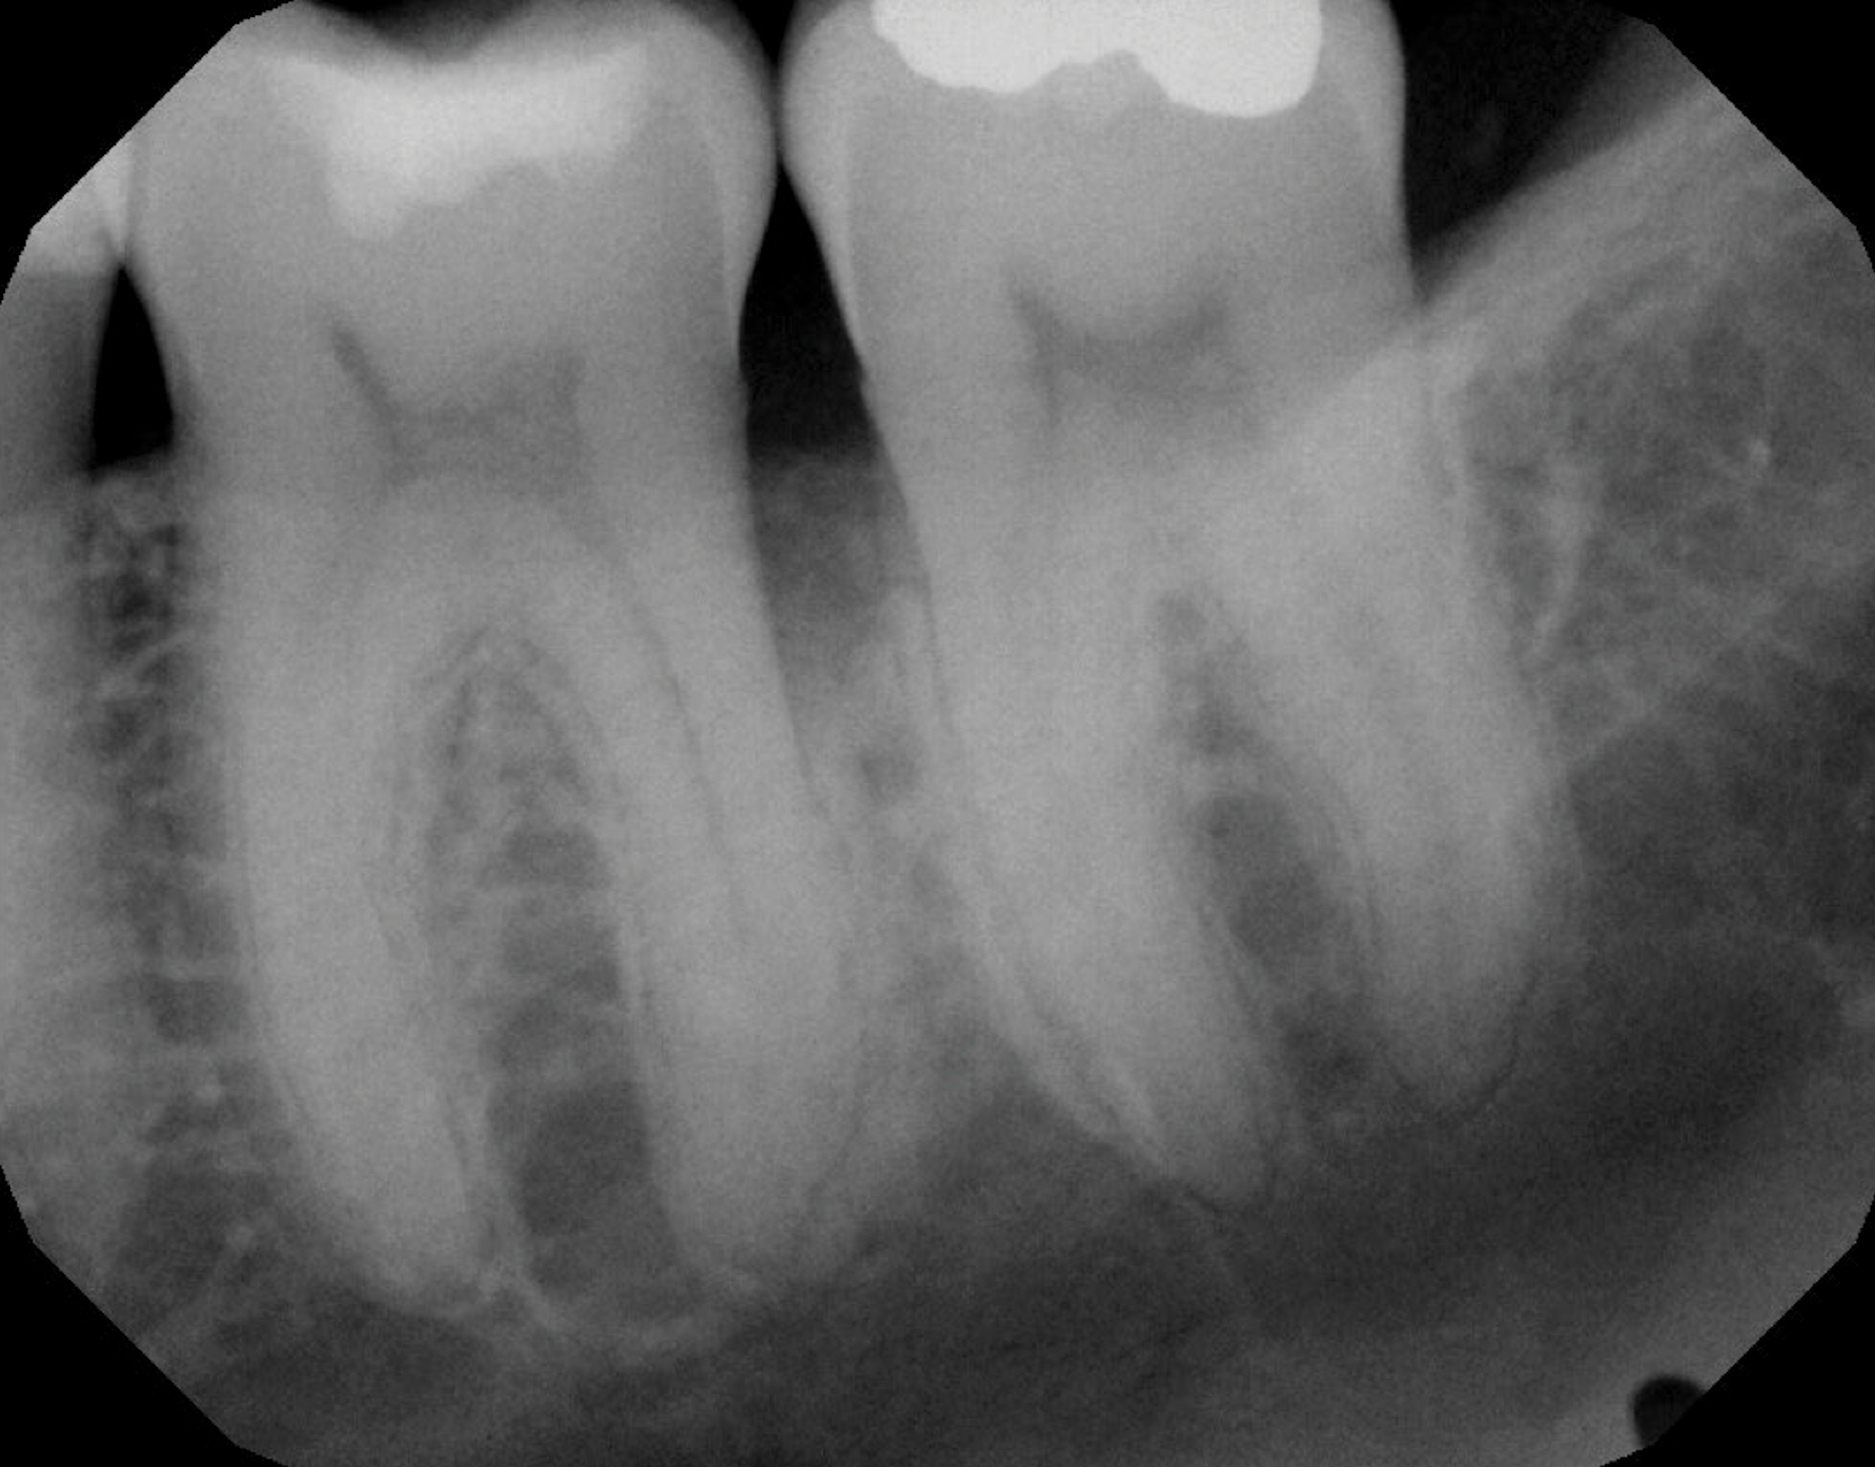

In the case presented, a 56-year-old healthy nonsmoking male patient, diagnosed with periodontitis stage III, localized, grade B, had been under care in a private practice periodontal office (RAL) for 25 years. He had a history of good compliance with his treatment (full-mouth plaque score <20%). During the COVID-19 pandemic, the patient missed three supportive periodontal therapy (SPT) visits over a year, resulting in periodontal breakdown interproximal between teeth Nos. 18 and 19 (mandibular left second and first molars, respectively). At his most recent periodontal maintenance visit, significantly increased periodontal probing depths of up to 10 mm with bleeding on probing were noted (Figure 1 through Figure 3). The periapical radiograph revealed a deep, narrow three-wall intrabony defect at the distal aspect of tooth No. 19, with class I buccal furcation involvement (Figure 4). According to the periodontal risk score (PRS),15 formerly known as the Miller-McEntire periodontal prognosis index, the tooth prognosis at the patient's initial examination was "good" (score = 5), taking into account that he was unaware of his hemoglobin A1C (HbA1c) levels. This scoring motivated the patient to be tested, and his follow-up HbA1c was <6%, thus reducing his PRS to 3, which was considered "excellent," as the PRS target goal for regenerative procedures is a score of <5.15

Fig 4. Periapical radiograph revealing a distal intrabony defect at tooth No. 19.

Figure 4